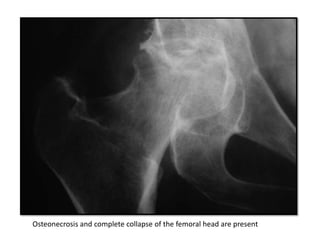

Concentric joint-space loss. Subchondral erosions and sclerosis of the

femoral head

Septic Arthritis…

The earliest plain film radiographic findings of septic arthritis are

soft tissue swelling around the joint and a widened joint space from

joint effusion.

Osteonecrosis and complete collapse of the femoral head are present